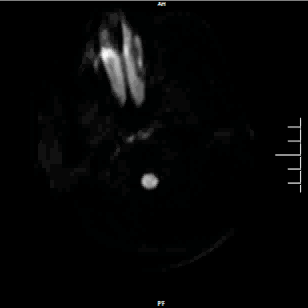

颅脑DWI

病历夹什么径技·第152期|串联营病历夹:川陕大营_https://www.jmylbn.com_新闻资讯_第40张

病历夹什么径技·第152期|串联营病历夹:川陕大营_https://www.jmylbn.com_新闻资讯_第41张

诊断:右侧放射冠区急性脑梗死。